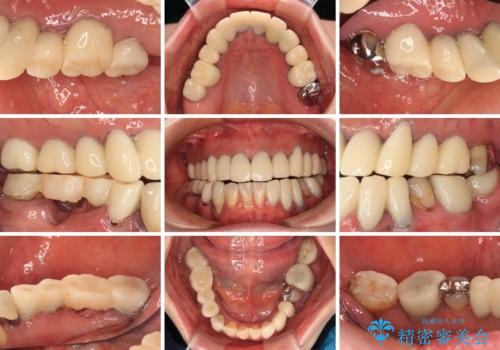

- 近医にて古いかぶせ物をセラミッククラウンにしようと治療を開始したものの、仮歯での咬み合わせが不安定とのことで、転院を希望して来院された患者様です。

骨格的に下顎骨が前方位に位置しており、上下前歯部の先端同士が接触する切端咬合でした。

このような方は咬み合わせが大きく変わると不安定となるため、まずは装着されている仮歯で咬合調整を行い、安定した咬み合わせとした後に、新しい仮歯に置き換え、その後オールセラミッククラウンにて補綴治療を行うこととしました。